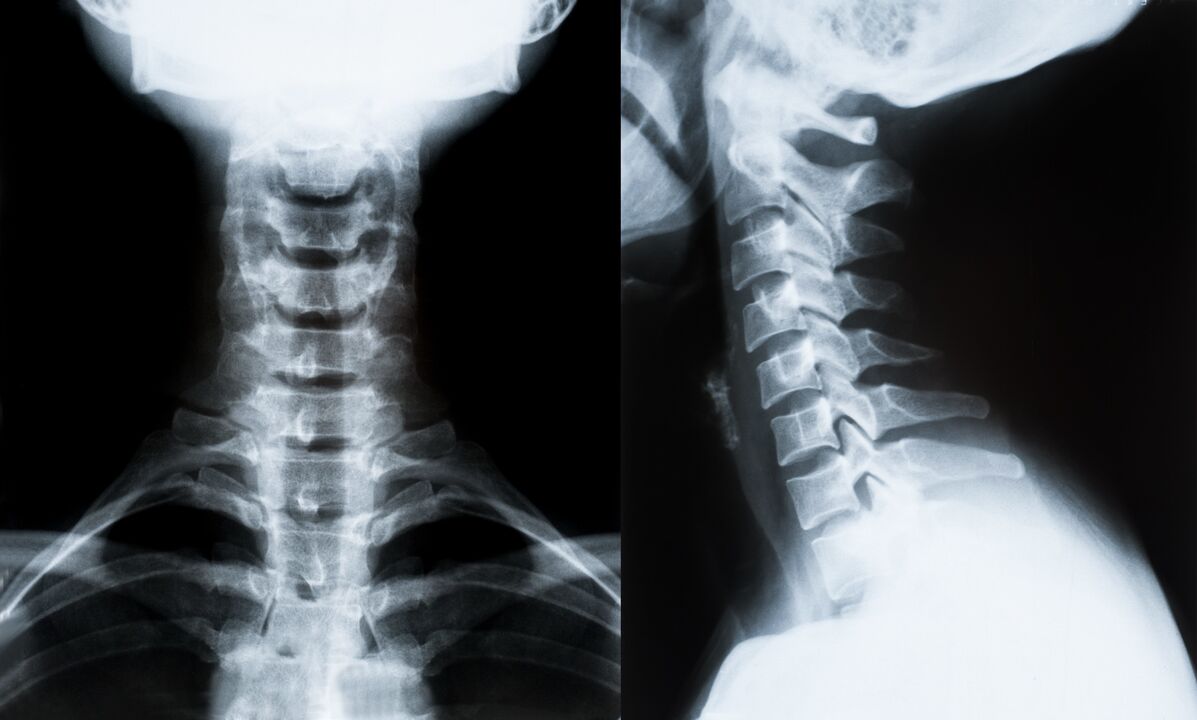

Peamised emakakaela lülisamba osteokondroosi diagnoosimise ja edasise ravi määramise meetodid:

- röntgen. Kõige vähem tõhus, kuid traditsiooniline diagnostikameetod.

- Magnetresonantstomograafia on kõige tõhusam diagnostiline meetod. Seda tüüpi patsiendi uurimisel on kõik vajalikud struktuurid nähtavad.

- Kui muutusi on vaja mõõta, kasutatakse kompuutertomograafiat. Määrab hernia ja muude asjade olemasolu.

- Viimane meetod on ultraheli dupleksskaneerimine. See uurimismeetod määrab verevoolu kiiruse arterites.

Seljaajuhaigust on kodus võimatu täpselt määrata.